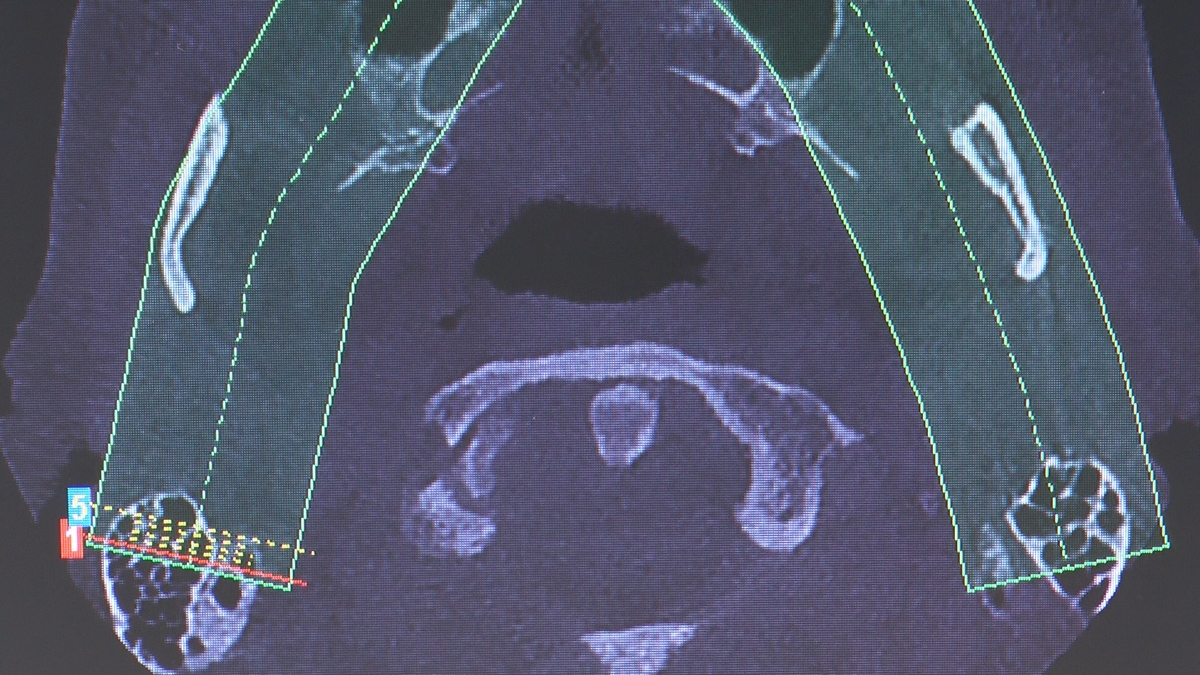

W trakcje dwóch dni zabiegowych, piątek i sobota, 5 i 6 października 2018 roku, lekarze uczestniczący w 6 Sesji VI Sezonu, wykonali wiele zabiegów o wysokim stopniu trudności. Przeprowadzili je pod kierunkiem Mentorów Instytutu Vivadental – dr n.med. Violetty Szycik, dr n.med. Magdaleny Kisłowskiej-Syryczyńskiej oraz dr Małgorzaty Piotrowskiej.

Wprowadziliśmy łącznie 25 implantów w tym wykonaliśmy:

zabiegi regeneracji kości z zastosowaniem materiałów kościozastępczych i kości własnej oraz fibryny bogatopłytkowej,